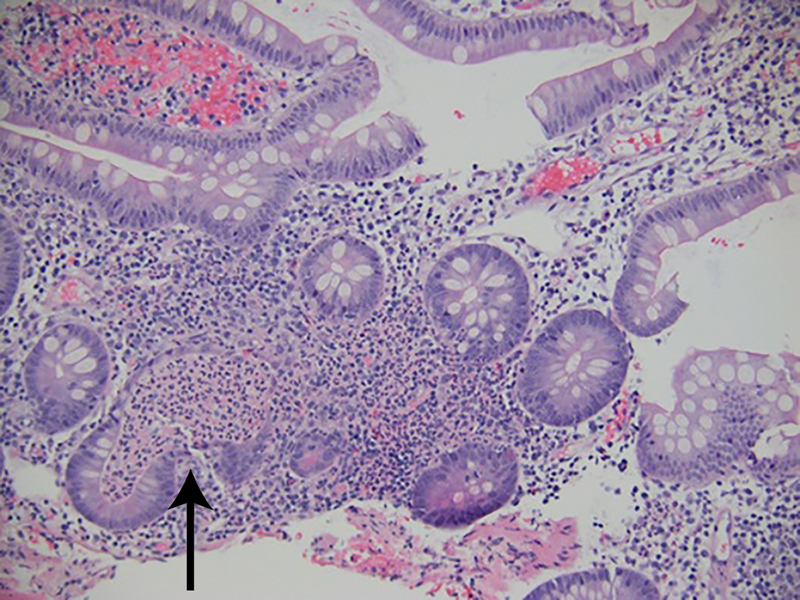

The patient underwent GI tract esophagogastroduodenoscopy 24 hours after admission. Results revealed severely inflamed, diffusely erythematous mucosa in the stomach (Figure 1A) and diffusely erythematous, congested mucosa with overlying exudate in the duodenum (Figure 1B). Gastric biopsy specimens demonstrated focally active gastritis without granuloma formation (Figure 2). Giemsa stain results were negative for Helicobacter pylori. Duodenal biopsy specimens showed active duodenitis with acute cryptitis, crypt abscess formation, and mild villous blunting without granulomas or viral inclusions (Figure 3). Results of colonoscopy with examination of the terminal ileum revealed mild colonic inflammation, extending from the rectum to the mid-ascending colon (Figure 4A). The most severe condition appeared to be in a rectosigmoid distribution. The proximal ascending colon and cecum appeared to be spared. The ileal mucosa appeared erythematous and edematous, with overlying exudate (Figure 4B). Biopsy specimens of the rectum, the sigmoid, and descending, transverse, and proximal ascending colon demonstrated mild active colitis with acute cryptitis, crypt abscesses, and neutrophils within the lamina propria (Figure 5). Biopsy specimens of the distal ileum showed moderate active ileitis with acute cryptitis, crypt abscesses, and focal architectural distortion (Figure 6).

Biopsy specimen of the distal ileum taken 2 weeks after ipilimumab administration showed active ileitis with acute cryptitis, crypt abscesses, and focal architectural distortion (hematoxylin-eosin, original magnification ×100).